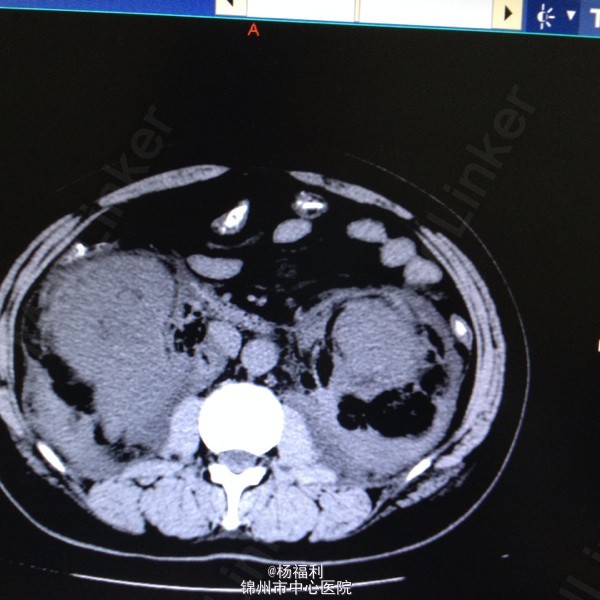

44岁女患。为消化科我会诊患者。 现病史:以上腹痛9小时为主诉入院。无发热及寒战、噁心未呕吐,无腹泻及黑便。 既往史:双眶炎性假瘤2年,口服激素治疗,并补钾。

查体:上腹部压痛,无反跳痛、右侧压痛明显,右肾区叩击痛,左肾区轻叩击痛,双输尿管走形区无压痛。 辅助检查;泌尿系彩超:双肾积水。 血白细胞:9.99*10^9。 肾功能正常。 全腹部ct及MRU检查:见图片。

诊断;真的不知道是啥病。 处理:暂时止痛处理。双肾病变。不知从哪里下手。